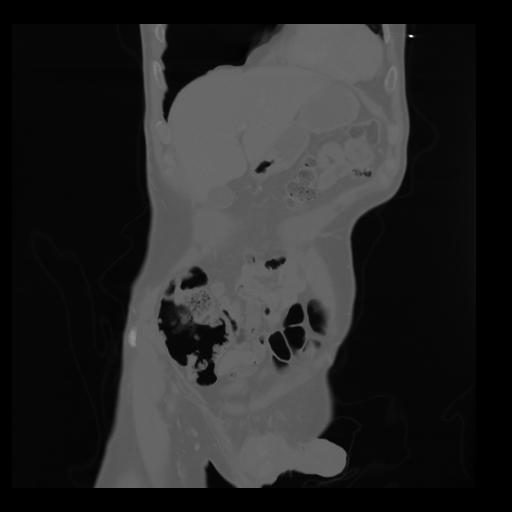

35 CUERPO,CE,Coronal,3.000,CUERPO,Coronal,